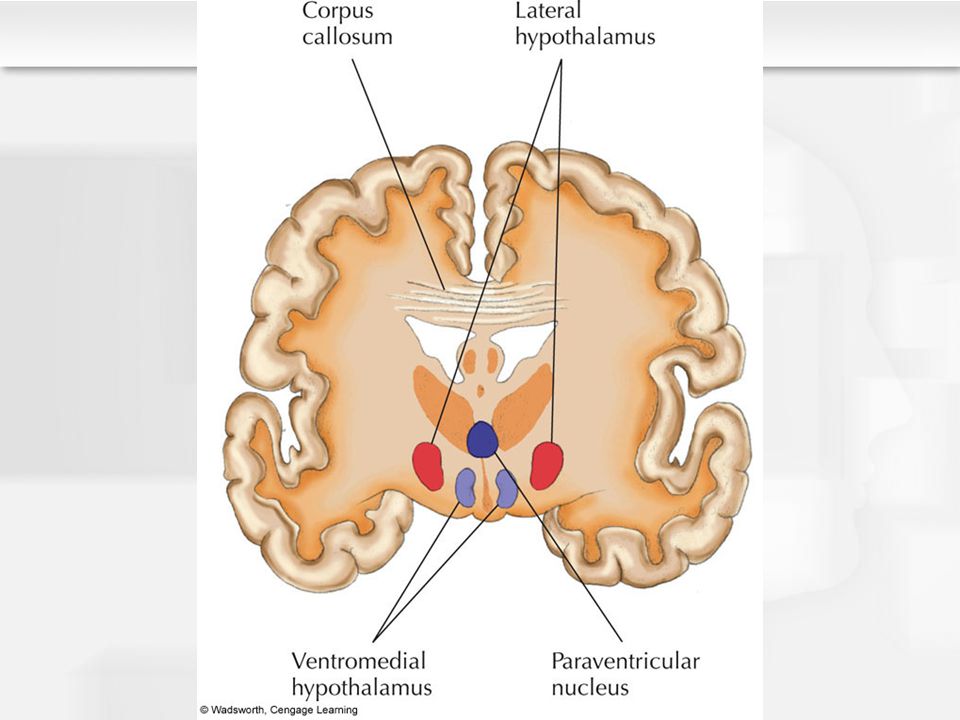

Как работает центр насыщения в гипоталамусе: визуальные иллюстрации